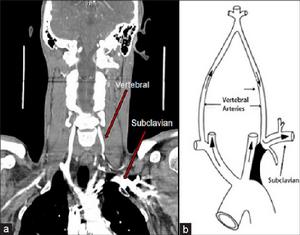

鎖骨下動脈盜血綜合徵是指椎動脈起始部近側段鎖骨下動脈或無名動脈狹窄或閉塞後,對側椎動脈血流經過基底動脈返流至患側椎動脈重新組成患側鎖骨下動脈遠側段的供血。其症狀是眩暈、眼花、走路不穩,有些人還會出現頭痛、頭枕部疼痛或聽力減退等。有些人“盜血”會出現於鎖骨下動脈或椎-基底動脈,甚至在大腦半球動脈,這時會出現輕度偏癱、失語等。

是一側鎖骨下動脈或無名動脈在椎動脈近心端顯著狹窄或閉塞,虹吸作用使同側椎血流逆流入鎖骨下動脈,也使對側椎動脈血流被部分盜取供應患肢,導致椎-基底動脈供血不足症狀。